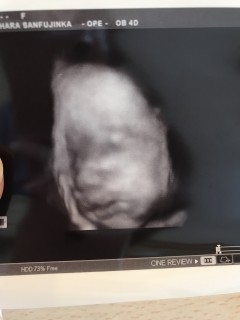

なかなかいつも顔を隠してばかりで今回も先生粘ってくれました(´・∀・`) だんだん目は旦那似かな? 鼻は私似かな?とか言いあってます(*´∀`*)

なかなか見れない週数に入りお顔を久々に見せてくれました!! 大きさは1860g程度、平均の大きさの女の子です。前回よりもお肉がついて赤ちゃんらしくなってきました。厚ぼったい唇は私に似ています。 目鼻立ちもしっかりしていると言われました!早く会いたくて仕方ないです。